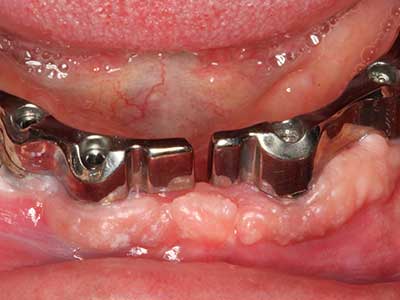

Si es preciso realizar intervenciones quirúrgicas en las que el hueso está en contacto directo con estructuras sensibles, como son los vasos sanguíneos o los nervios, los instrumentos rotativos presentan un enorme potencial de provocar lesiones iatrogénicas. Así, precisamente en la representación de nervios después de una lesión iatrogénica, o en el transcurso de la lateralización de un nervio para resecciones, reconstrucciones o incorporación de implantes, los equipos piezoeléctricos pueden resultar muy útiles para preparar la tapa ósea y retirar las partes de tejido duro cercanas al nervio (fig. 17-20). Por lo general, un ligero contacto del cordón nervioso con el inserto piezoeléctrico no tiene consecuencia alguna; ahora bien, un procedimiento poco cuidadoso con movimientos tipo sierra o piezas de trabajo sobre la base ósea aún existente puede provocar lesiones nerviosas temporales o incluso permanentes. Con todo, el riesgo de sufrir una lesión de este tipo se considera significativamente inferior que en los casos en los que se utilizan sierras y fresas (Pereira, Gealh et al. 2014).

Aplicación: Terapia periodontal